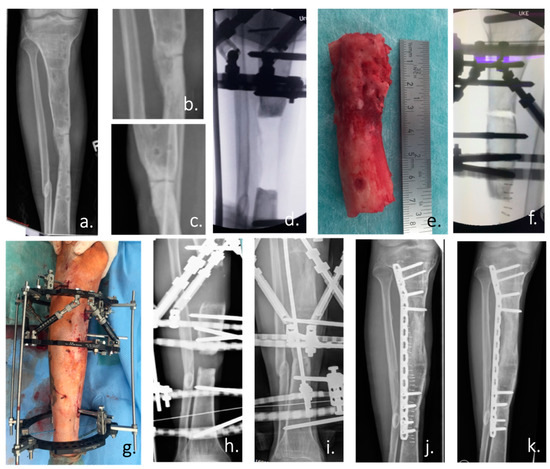

- Cox, G.; McGonagle, D.; Boxall, S.A.; Buckley, C.T.; Jones, E.; Giannoudis, P.V. The use of the reamer-irrigator-aspirator to harvest mesenchymal stem cells. J. Bone Joint Surg. Br. 2011, 93-B, 517–524. [Google Scholar] [CrossRef]

- Madison, R.D.; Nowotarski, P.J. The Reamer-Irrigator-Aspirator in Nonunion Surgery. Orthop. Clin. N. Am. 2019, 50, 297–304. [Google Scholar] [CrossRef]

- Calori, G.M.; Colombo, M.; Mazza, E.L.; Mazzola, S.; Malagoli, E.; Mineo, G.V. Incidence of donor site morbidity following harvesting from iliac crest or RIA graft. Injury 2014, 45, S116–S120. [Google Scholar] [CrossRef]

- Schmidmaier, G.; Herrmann, S.; Green, J.; Weber, T.; Scharfenberger, A.; Haas, N.P.; Wildemann, B. Quantitative assessment of growth factors in reaming aspirate, iliac crest, and platelet preparation. Bone 2006, 39, 1156–1163. [Google Scholar] [CrossRef]